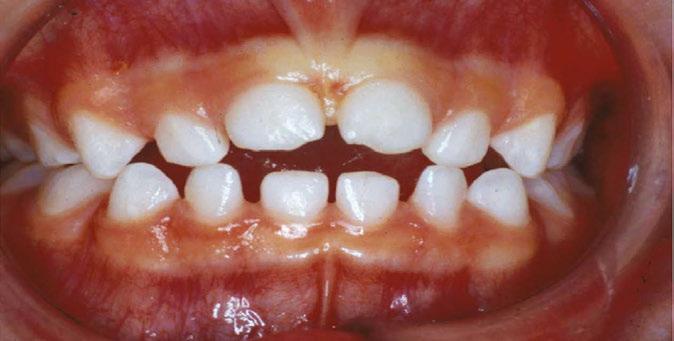

Dx: SRDB-Malocclusion Co-morbidity: Pre-WW II Physician-Dentist Collaboration

There are numerous pre-WW II papers published within the corpus of medical and dental literature that support the practice of physicians and dentists collaboratively diagnosing and treating SDB and malocclusion co-morbidity, mostly skeletal-dental maxillary transverse deficiency and mandibular distal occlusion (retrusion/retrognathia) through the ‘spreading of the deciduous arches’ during the early childhood years (30 months-7 y.o./complete primary-early mixed dentitions).2,8 These interventions had been carried out for the primary purpose of improving nasal breathing and quality of life rather than solely for the purpose of correcting so-called ‘irregularities of the teeth’. As these historically important journal articles pre-dated the 1948 initial published report of an RCT by several decades, it is unreasonable to criticize their usefulness compared to current RCT standards. Developing malocclusions are nearly always first detectable in the primary dentition (ages 2.5-7 yrs),9,10 nearly always become more complex (i.e., get worse) with age without appropriate intervention,9 and are very frequently co-morbid with pediatric sleep related breathing disorders (SRBD). In the single-digit growth

years they are non-surgically correctible with validated orthodontic/dentofacial orthopedic interventions. It seems reasonable to suggest that failure to diagnose and appropriately treat or refer afflicted young children is a medically-indefensible position.

In 2017, the ADA House of Delegates approved a policy statement on the role of dentists in treating SRBD.11 Key components include assessing a patient’s risk for SRBD as part of a comprehensive medical and dental history and referring affected patients to appropriate physicians. Specifically, the policy statement refers to the screening of children: In children, screening through history and clinical examination may identify signs and symptoms of deficient growth and development, or other risk factors that may lead to airway issues. If risk for SRBD is determined, intervention through medical/dental referral or evidenced based treatment may be appropriate to help treat the SRBD and/or develop an optimal physiologic airway and breathing pattern. It is widely believed that current dental education does not prepare dentists to recognize pediatric airway issues. Standardized methods of screening with recognized thresholds for referral are not currently available. Development of these metrics would displace the subjective criteria that are currently used and provide a common language for every provider on the child’s health care team. Contemporaneous educational materials on the screening methods and the significant signs of pediatric airway issues would benefit the dental community and public.

In a lecture held in 2018 at Boston University entitled ‘Sleep Disordered Breathing/Obstructive Sleep Apnea Symposium’,21 a new screening tool called C.H.I.C.A.G.O. H.E.A.R.T.S. (C.H.) had been introduced as potentially becoming the first validated screening device specifically designed to identify CFRC physical traits that can often be comorbid with SRBD. Several of these traits are listed within the C.H. acronym (Fig. 2). For instance, under the first letter ‘C’ are listed: Crossbite 22,23 Fig. 3 and Crowded Pharynx;24,25 ‘H’: Hyper-divergent growth (Fig. 4),16 Hypertrophic tonsils and/or adenoids;26,27 ‘I’: Incompetent lips;28 ‘C’: Constricted arches (Fig. 5);23,29,30 ‘A’: Airway anatomy (Fig. 6);22,31 ‘G’: Grinding teeth (bruxism)32 and Gonial angle excess;33 ‘O’: Overweight child34 and Obtuse nose-lip angle( NLA);35 ‘H’: Highly-vaulted palate;36 ‘E’: Ezcema-atopia37 and Eye appearance-venous pooling38 and scleral show;39 ‘A’: Anterior open-bite